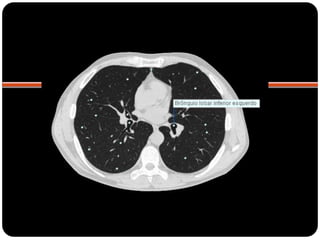

TC com janela para parênquima

Brônquios segmentares

Esquerdo



Pulmão direito

Superior: direito

inferior: esquerdo

 Pulmão direito:

 LSD: anterior, apical e posterior;

 LM: medial e lateral;

 LID: superior, basal medial, basal lateral,

basal anterior, basal posterior;

 Pulmão esquerdo:

 LSE: apicoposterior, anterior,

superior(língula), inferior(língula);

 LIE: segmento superior, basal antero-

medial, basal lateral e basal posterior;